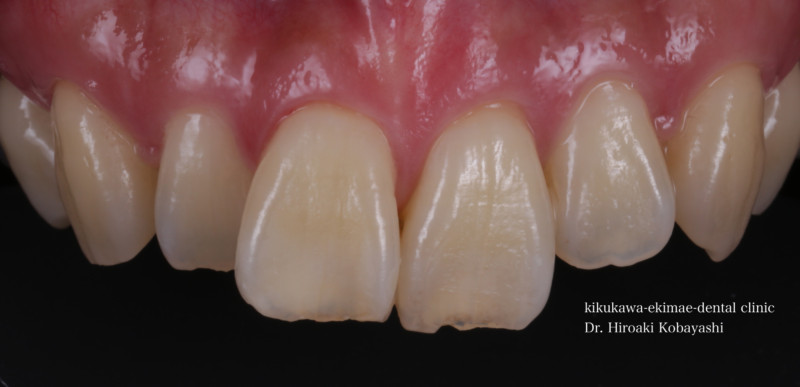

歯並びを気にされて来院されました。見た目改善を目的にワイヤーによる部分矯正を希望されました。 ブラケット装着用のマウスピースを作り、ブラケット装着を行います。   弱い力をかけながら、ワイヤーにより歯を動かします。強い力を急にかけると歯の根が吸収されてしまいます。なので弱い力で歯を動かすことによって根への負担が少なく歯根吸収のリスクが少なくなります。               6ヶ月程度で歯の並びを改善することができました。   before after